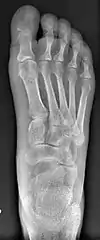

![]() Fig. 8a. Painful hallux valgus and metatarsus primus varus deformities recurrence of left foot after osteotomy surgery | |

- For recurrence correction after osteotomy procedure (Fig. 8)

Late deformity recurrence can happen after osteotomy (bone-breaking) procedures because osteotomy surgeries do not specifically stabilize first metatarsal bone.